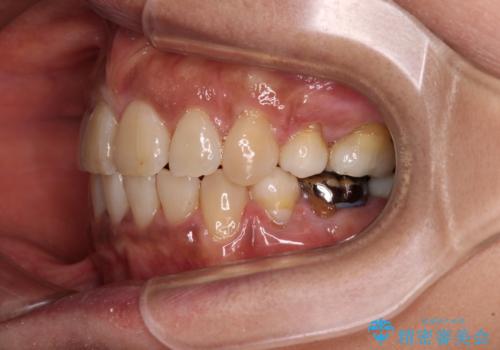

- 八重歯やクロスバイトを気にして来院された患者様です。

口元の突出感はありませんでしたが、デコボコが強く、非抜歯矯正とすると出っ歯仕上がりとなる可能性があったため、上下左右の第一小臼歯4本を抜歯し、ワイヤー装置にて矯正治療を行うこととしました。